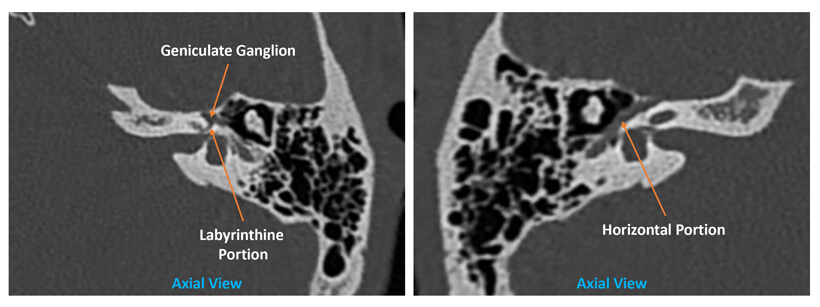

Figure 2. Facial nerve anatomy in the temporal bone.

The status of the ossicles preoperatively will enable the surgeon to consent the patient regarding the options available and risk involved with ossiculoplasty ranging from incus transposition to prosthesis replacement. Signs suggestive of otosclerosis, such as thickening of the stapes footplate or fissula ante fenestram, should be assessed too [7]. The integrity of the semicircular canals is of concern when the patient presents with vertigo and positive fistula test. The specificity and sensitivity of the CT temporal bone to detect lateral semicircular canal dehiscence status is high [2]. Knowing this early on will empower the surgeon to consent the patient regarding the risk involved and the possibility of CWD mastoidectomy [5]. The lateral semicircular canal status will be the primary concern for any cholesteatoma cases as complete removal of the cholesteatoma matrix could jeopardise the labyrinthine and hearing function on that side. Meanwhile, most dehiscence of the facial nerve occurs at the horizontal portion (Figure 2) in the middle ear which can be better appreciated on the axial view [1].